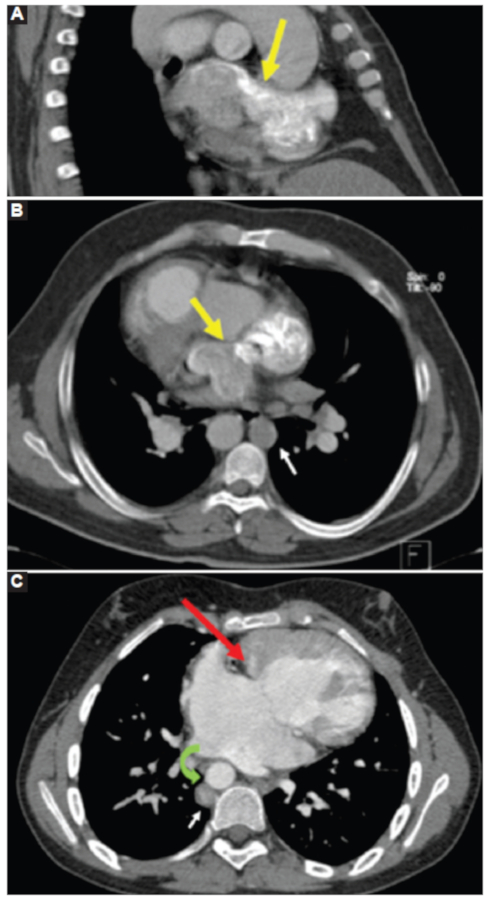

Corazón

En el caso 2 se observó dextrocardia con ambas aurículas de morfología izquierda y comunicación interauricular tipo seno venoso adyacente a la inserción de la vena cava superior. En un tiempo precoz luego de la administración de medio de contraste se demostró opacificación de la aurícula contralateral, lo que sugiere shunt derecha-izquierda (Fig. 2 A y B). En el caso 3 se evidenció corazón unicameral con canal auriculoventricular (Fig. 2C).